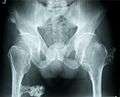

Hereditary multiple exostoses (HME or MHE), also known as diaphyseal aclasis, is a rare medical condition in which multiple bony spurs or lumps (also known as exostoses, or osteochondromas) develop on the bones of a child. HME is synonymous with multiple hereditary exostoses and multiple osteochondromatosis, which is the preferred term used by the World Health Organization.

It is characterized by the growth of cartilage-capped benign bone tumours around areas of active bone growth, particularly the metaphysis of the long bones. Typically five or six exostoses are found in upper and lower limbs. Most common locations are:[1]

HME can lead to the shortening and bowing of bones; affected individuals often have a short stature. Depending on their location the exostoses can cause the following problems: pain or numbness from nerve compression, vascular compromise, inequality of limb length, irritation of tendon and muscle, Madelung's deformity[2] as well as a limited range of motion at the joints upon which they encroach. A person with HME has an increased risk of developing a rare form of bone cancer called chondrosarcoma as an adult.[2] Problems may be had in later life and these could include weak bones and nerve damage.[3][4][5] The reported rate of transformation ranges from as low as 0.57%[6] to as high as 8.3% of people with HME.[7]